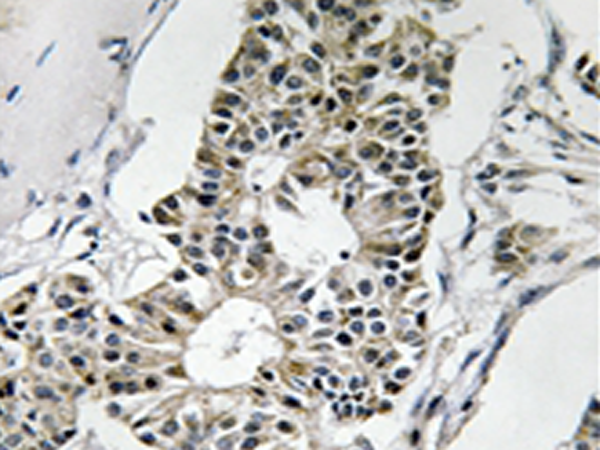

IHC positive control:

Human breast carcinoma tissue

IHC Recommend dilution:

50-100